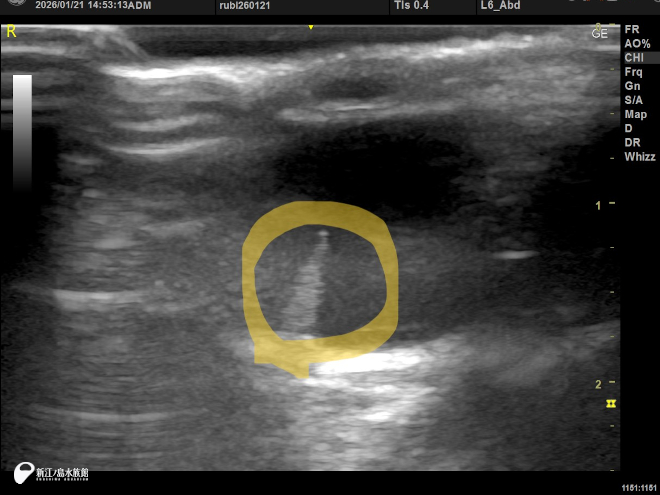

先日、獣医師によるフンボルトペンギンの目の検査をおこないました。

その際に眼底検査などができる機器や超音波診断機を使って眼球を調べるのですが、小学生の頃に絵でしか見たことのなかった、あの櫛状突起を見ることができました。そして獣医師よりペクテンという何やらかわいらしい言葉まで!? 櫛状突起のことを“ペクテン”というのだそうです。生きているペンギンの生ペクテンです。

フンボルトペンギンのペクテン 超音波診断による画像フンボルトペンギンのペクテン 超音波診断による画像

このペクテンですが、実はまだその役割がよくわかっていないものでもあるのです。小学生の時に見た本では、視細胞が集まっていてここで解像度を上げることができる的なニュアンスだったと思うのですが、今回調べてみると、鳥は網膜内には血管が少なく、このペクテンに血管が集約されて網膜に栄養を供給し視力解像度を上げているようなのです。う~んまだよくわからない?